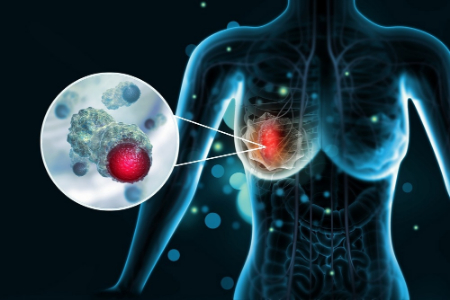

سرطان سینه نوعی سرطان است که از بافت سینه شروع می شود. علائم رایج سرطان سینه عبارتند از:

سرطان سینه اغلب باعث تغییرات پوستی در سینه ها می شود. علائم احتمالی پوستی سرطان سینه عبارتند از:

دلایل متعددی برای تغییرات پوستی روی سینه وجود دارد. سرطان سینه ممکن است باعث علائم پوستی مانند قرمزی، التهاب، ضخیم شدن، فرورفتگی و تحریک شود. آکنه سینه به صورت برجستگی های کوچک قرمز، از جمله جوش های سر سفید، سر سیاه، پاپول و پوسچول ظاهر می شود. آکنه سینه به طور کلی بهبود می یابد، در حالی که علائم سرطان سینه با گذشت زمان بدتر می شوند. در صورت مشاهده تغییرات اخیر در سینههای خود به پزشک مراجعه کنید.